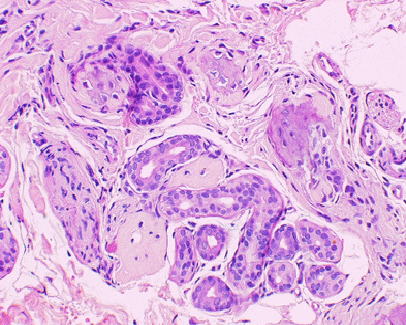

La

biopsia cutanea della cute del dorso, rilevava a livello del

derma scarsissimo infiltrato linfocitario perivascolare,

calcificazioni e aspetti di ossificazione nel derma reticolare,

prevalentemente a disposizione periannessiale (Figura

3).

Figura

3. Biopsia della cute del dorso: aspetti di ossificazione nel

derma, attorno alle ghiandole sudoripare (ematossilina e eosina100x)